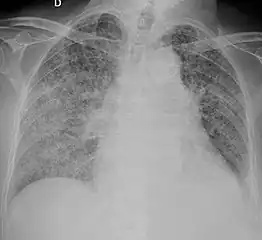

Chest X ray showing miliary tuberculosis

Miliary tuberculosis is a form of tuberculosis that is characterized by a wide dissemination into the human body and by the tiny size of the lesions (1–5 mm). Its name comes from a distinctive pattern seen on a chest radiograph of many tiny spots distributed throughout the lung fields with the appearance similar to millet seeds—thus the term "miliary" tuberculosis. Miliary TB may infect any number of organs, including the lungs, liver, and spleen.[2] Miliary tuberculosis is present in about 2% of all reported cases of tuberculosis and accounts for up to 20% of all extra-pulmonary tuberculosis cases.[3]

Testing for miliary tuberculosis is conducted in a similar manner as for other forms of tuberculosis, although a number of tests must be conducted on a patient to confirm diagnosis.[4] Tests include chest x-ray, sputum culture, bronchoscopy, open lung biopsy, head CT/MRI, blood cultures, fundoscopy, and electrocardiography.[10] The tuberculosis (TB) blood test, also called an Interferon Gamma Release Assay or IGRA, is a way to diagnose latent TB. A variety of neurological complications have been noted in miliary tuberculosis patients—tuberculous meningitis and cerebral tuberculomas being the most frequent. However, a majority of patients improve following antituberculous treatment. Rarely lymphangitic spread of lung cancer could mimic miliary pattern of tuberculosis on regular chest X-ray. [15]